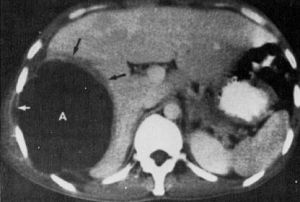

5、肝脏显影 超声波探查无创伤,准确方便,成为诊断肝脓肿的基本方法。脓肿所在部位显示与脓肿大小基本一致的液平段,并或作穿刺或手术引流定位,反复探查可观察脓腔的进展情况。B型超声显像敏感性高,但与其它液 医学百科网 | YxBaike.Com

性病灶鉴别较困难,需作动态观察。CT、肝动脉造影、放射性核素肝扫描、核磁共振均可显示肝内占位性病变,对阿米巴肝病和肝癌、肝囊肿鉴别有一定帮助,其中CT尤为方便可靠,有条件者可加选用。